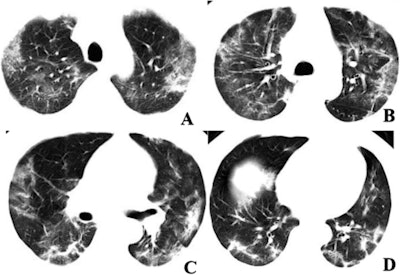

In the case of one 29-year-old male, the initial DNA test was negative for 2019-nCoV and so was the follow-up DNA test performed several days later. His CT scans showed multifocal mixed ground-glass opacities and parenchymal consolidation involving the subpleural regions of both lungs. The patient was not admitted to the hospital for isolated treatment until a third DNA test based on a sample collected eight days after initial presentation turned out positive for the virus.